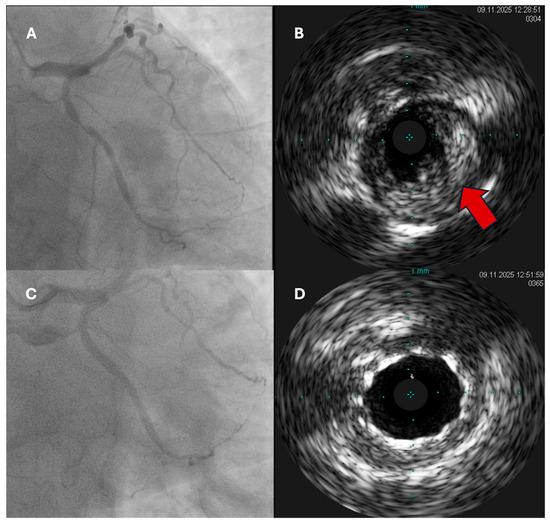

Background: Acute coronary syndromes (ACSs) remain a leading cause of death and disability. Since the publication of the 2023 ESC ACS guidelines, multiple studies and an ESC/EAS dyslipidaemia update have refined how clinicians diagnose, revascularize, and treat ACS across the care continuum. Content: This state-of-the-art review synthesizes advances from 2023 to 2025 across five domains. Diagnosis: High-sensitivity troponin-based accelerated pathways remain foundational; GRACE 3.0 improves calibration for early vs. delayed angiography, while selective use of CCTA and routine use of intracoronary imaging/physiology help define the mechanism and optimize PCI. Revascularization: complete revascularization continues to underpin care in multivessel disease, with recent data favouring culprit-only PCI acutely and staged non-culprit treatment during the index stay in most STEMI presentations, particularly with heart-failure physiology. Antithrombotic therapy: Aspirin remains critical early after ACS-PCI; emerging evidence supports shorter DAPT and aspirin withdrawal after 1 month in carefully selected, low-ischaemic-risk patients, whereas day-0 aspirin-free strategies in unselected ACS are not non-inferior. Secondary prevention: A “strike early and strong” approach to LDL-cholesterol—often with combination therapy in hospital—is emphasized, alongside nuanced roles for SGLT2 inhibitors and GLP-1 receptor agonists. Special populations and implementation: Sex- and age-aware tailoring (including MINOCA/SCAD evaluation), pragmatic bleeding-risk mitigation, digitally enabled cardiac rehabilitation, and registry-driven quality improvement translate evidence into practice. Summary: Contemporary ACS care is moving from uniform protocols toward risk-stratified, mechanism-informed pathways. We offer practical algorithms and checklists to align interventional timing, antithrombotic intensity/duration, and secondary prevention with individual patient risk—bridging new evidence to bedside decisions. Full article

Show Figures

Figure 1